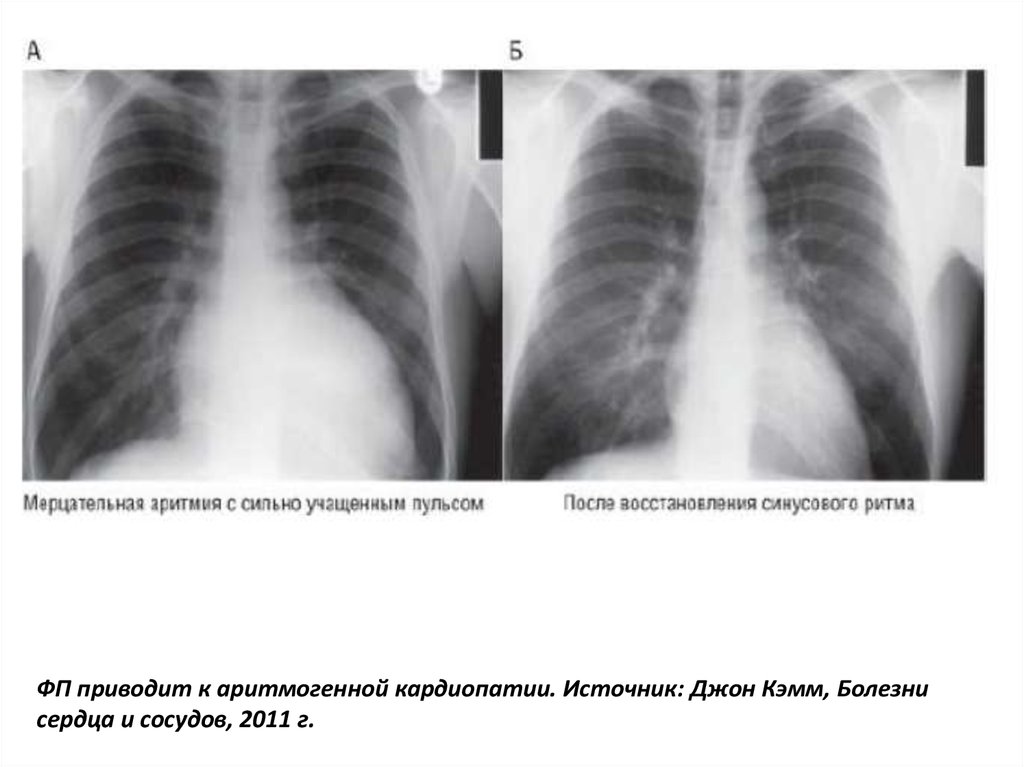

ФП приводит к аритмогенной кардиопатии. Источник: Джон Кэмм, Болезни

сердца и сосудов, 2011 г.